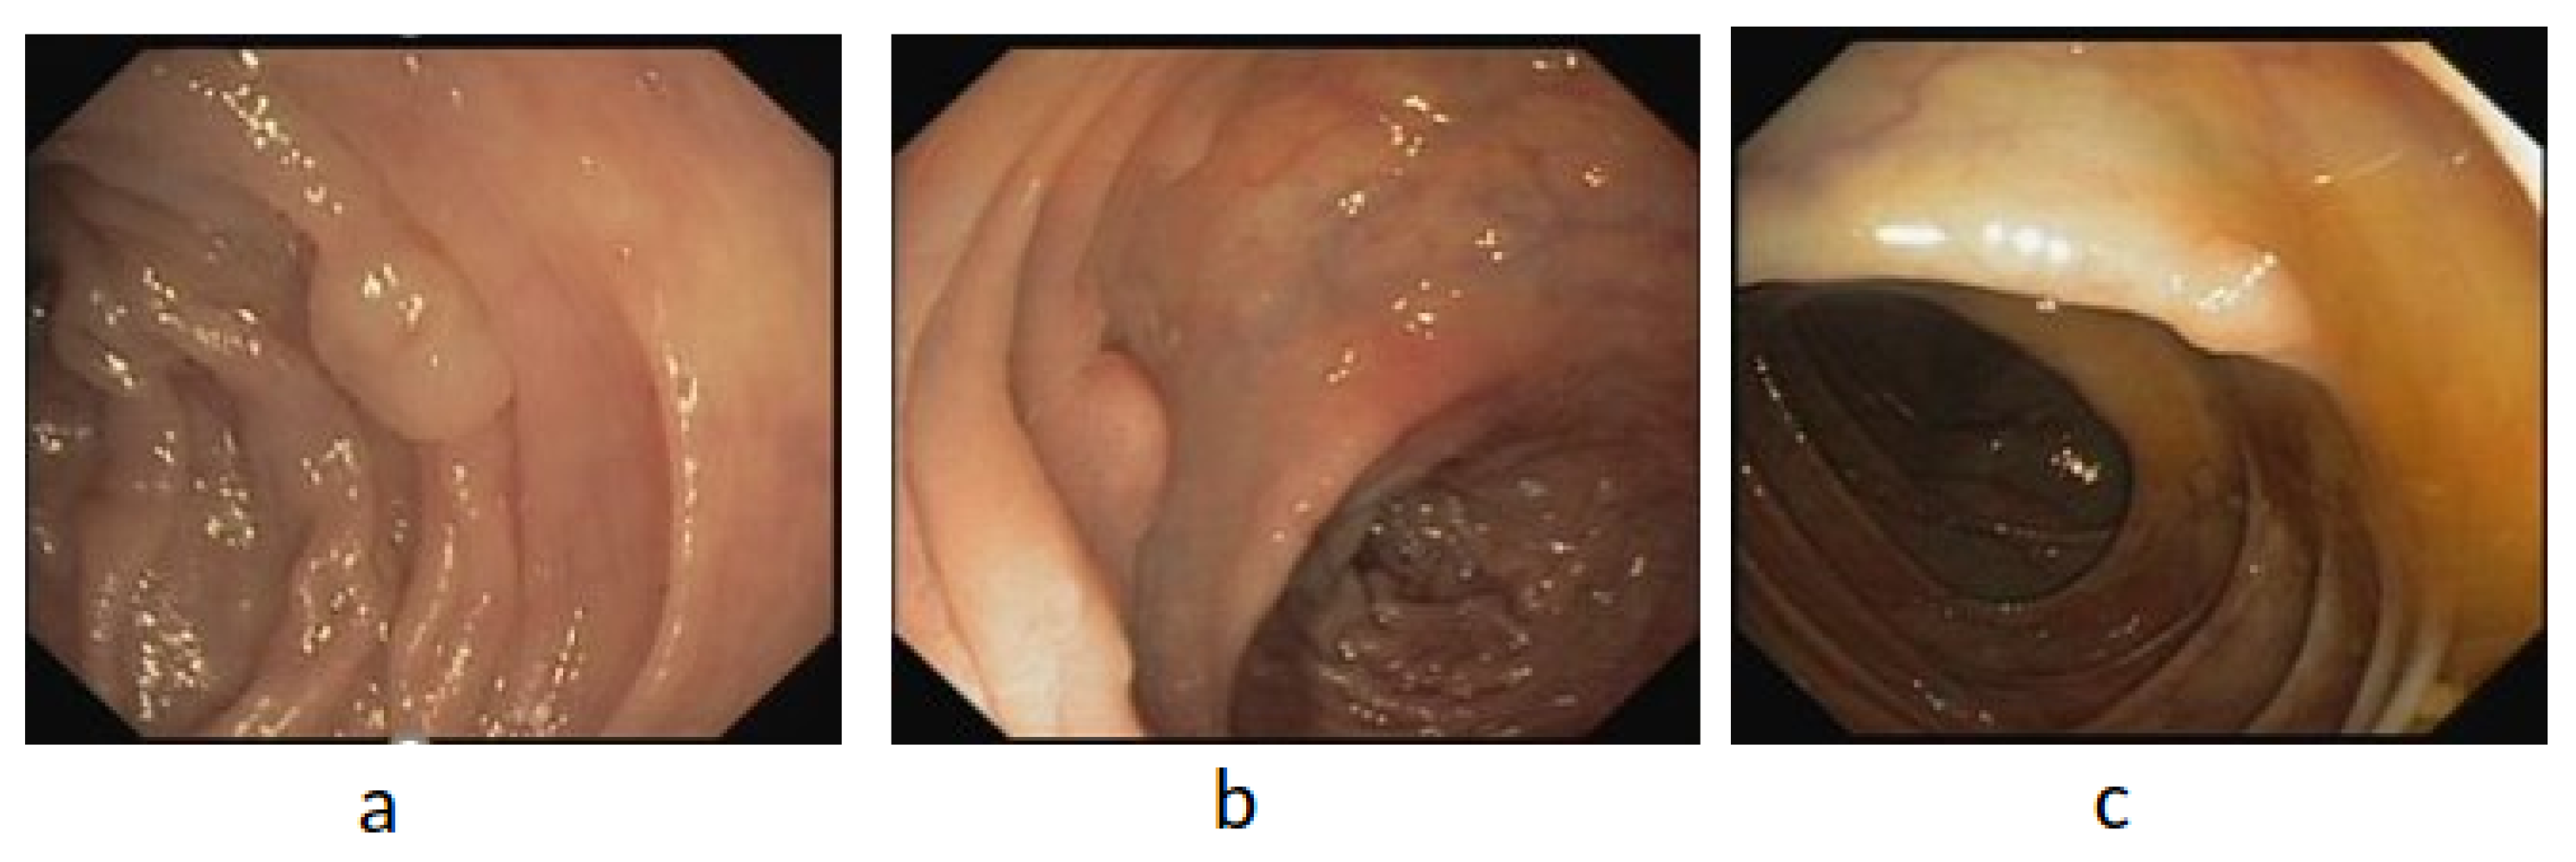

Figure 7.

Example of WCE polyp images (a–c).

The Fist WCE dataset was acquired from PillCam©COLON 2 polyps [49]. The original image’s resolution was 256 pixels × 256 pixels. As depicted in Figure 7, the WCE dataset contains 120 polyps and 181 normal images obtained from one patient’s VCE test. To avoid the overfitting problem owing to the small dataset size, we increased the training dataset size by the pre-processing step, as described in this section. Therefore, the revised dataset included 1250 polyp patches and 1864 normal patches. Subsequently, two trained experts reviewed and manually defined binary masks corresponding to the polyp regions covered to provide ground truths after being manually labeled and annotated as positive and negative samples. The ground truth bounding box was drawn based on the mask ground truth provided by specialists to meet the requirements of the polyp detection tools, using a graphical image annotation tool and label object bounding boxes in images (LabelImg) and corrected by experts. A popular colonoscopy dataset called CVC-ClinicDB [50] was also used in this work, which contained frames showing polyp regions of different shapes. A total of 25 colonoscopy videos were used by researchers to select at least 29 sequences containing one polyp region in every frame. Subsequently, a set of frames was selected for each sequence. As depicted in Figure 8, the CVC-ClinicDB dataset comprises 612 polyp images (size: 384 × 288; format: tiff). Experts created the ground truth by manually defining masks corresponding to the regions covered by the polyps in each frame. To meet the requirements of polyp detection tools, the ground truth bounding box was drawn based on the ground truth provided by specialists. The annotated ETIS-Larib [51] dataset was used to assess the detection results. A total of 34 colonoscopy videos were used to generate 196 polyp images of different shapes and sizes. The ground truths of the ETIS-Larib dataset were annotated by competent endoscopists members of clinical institutions as depicted in Figure 9. The colonoscopy CVC-ClinicDB [52] and ETIS-Larib [53] datasets were adopted in the 2015 MICCAI sub-challenge on automatic polyp detection. The normal and abnormal images were rescaled to 299 × 299 pixels to reach the pre-trained inception v4 network input size. We split the data into training 70%, validation 10%, and model testing 20%. The five-fold cross-validation [54] was used, in which the state and convergence of the model were checked after each epoch was completed. The hyperparameter number of iterations and learning rate were adjusted automatically during the validation data. In general, the validation set only adjusts the hyperparameters, such as the number of iterations and learning rate. Subsequently, they were adopted according to the five group performances in the models. The results were then averaged over the splits to estimate the mean average precision metric.